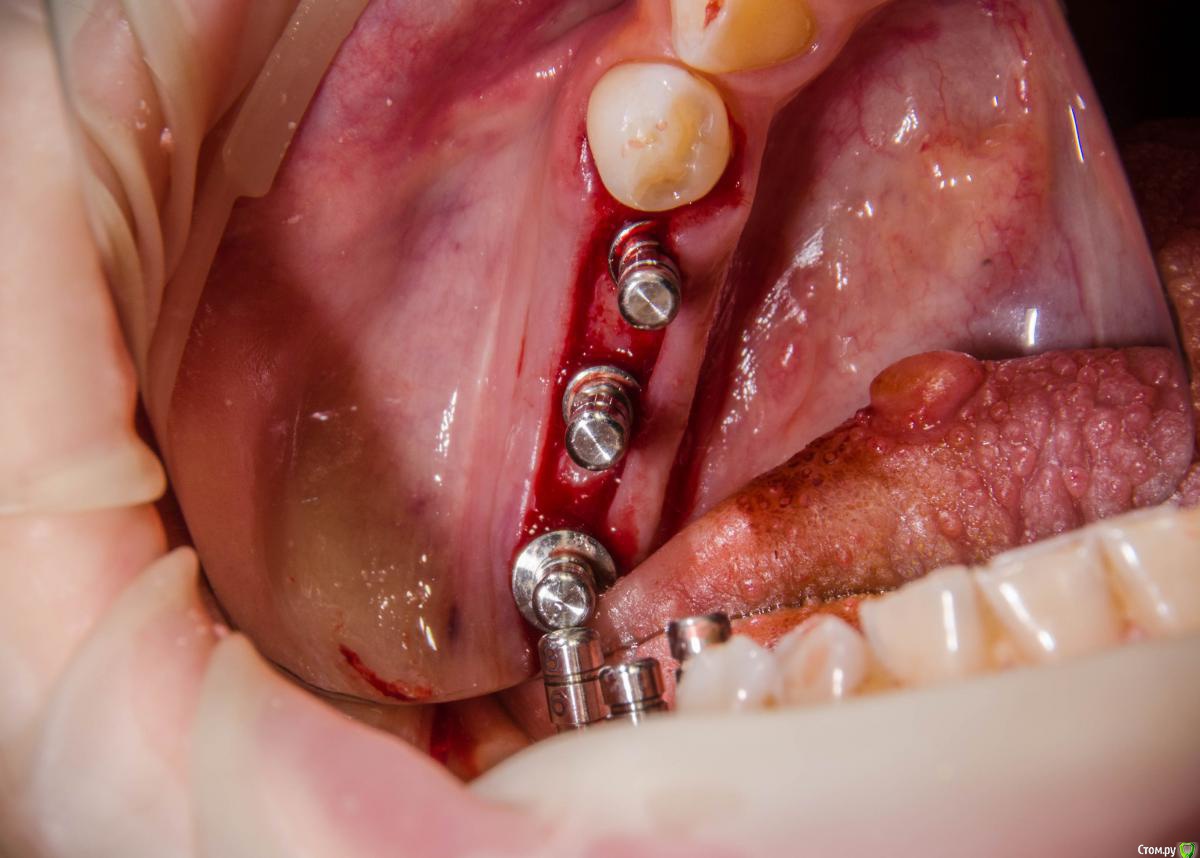

red_butler Опубликовано 7 февраля, 2017 Поделиться Опубликовано 7 февраля, 2017 когда до языка доберетесь? 1 Ссылка на комментарий

Astronaft Опубликовано 8 февраля, 2017 Поделиться Опубликовано 8 февраля, 2017 когда до языка доберетесь?Хороший вопрос. Как фибромы языка вырезать: по кругу ? И как потом заживает? Ссылка на комментарий

kamranchick Опубликовано 8 февраля, 2017 Автор Поделиться Опубликовано 8 февраля, 2017 когда до языка доберетесь?у нее 8 лет уже такая штучка, не растет и не мешает. а так, я думаю либо получать доступ как в Фрагискосе написано, либо коагулятором Ссылка на комментарий

surf Опубликовано 8 февраля, 2017 Поделиться Опубликовано 8 февраля, 2017 Все же, думаю,карлосс бы здесь расщеплял и добавлял)Десна хорошо получилась Ссылка на комментарий